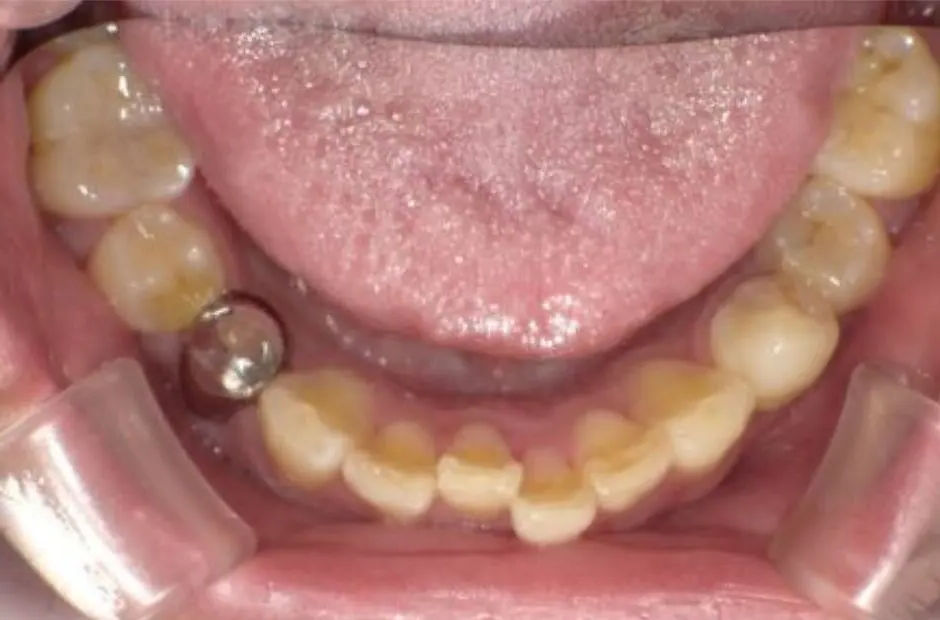

case.01

金属アレルギー治療の症例・治療前写真(銀歯1本)

金属アレルギー治療の症例・治療後写真(銀歯1本)

「 見た目の印象も変わる 」

口腔内のメタル除去で、見た目も劇的に変わります。金属を自然な素材に替えることで、笑顔が明るく、自信を持って会話できるように。印象を変えたい方は、おすすめです。

治療内容 古い銀歯を取り除き、代わりにe-maxクラウンを装着

治療期間/回数 1ヶ月/通院3回

費用 88,000円(税込、検査・診断、手術関連処置費用等は含まない)e-maxクラウン:88,000円/1カ所

リスク/副作用 咬合による割れ